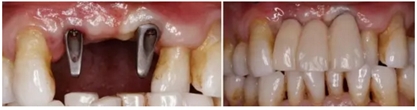

(2)數(shù)字化3D種植外科導(dǎo)板的設(shè)計制作

(3)數(shù)字化3D種植外科導(dǎo)板引導(dǎo)下Straumann 3.3x12 NC 種植體行延期種植

(5)個性化基臺及臨時修復(fù)體戴入,軟組織成形

美學(xué)區(qū)連續(xù)多牙缺失使術(shù)者臨床操作中缺乏直觀的植入?yún)⒖紭?biāo)志,會產(chǎn)生嚴重的美學(xué)風(fēng)險。以修復(fù)為導(dǎo)向設(shè)計配合3D打印技術(shù)的數(shù)字化種植外科導(dǎo)板,保證了種植體三維位置的精確,為種植體長期穩(wěn)定性提供了保障。